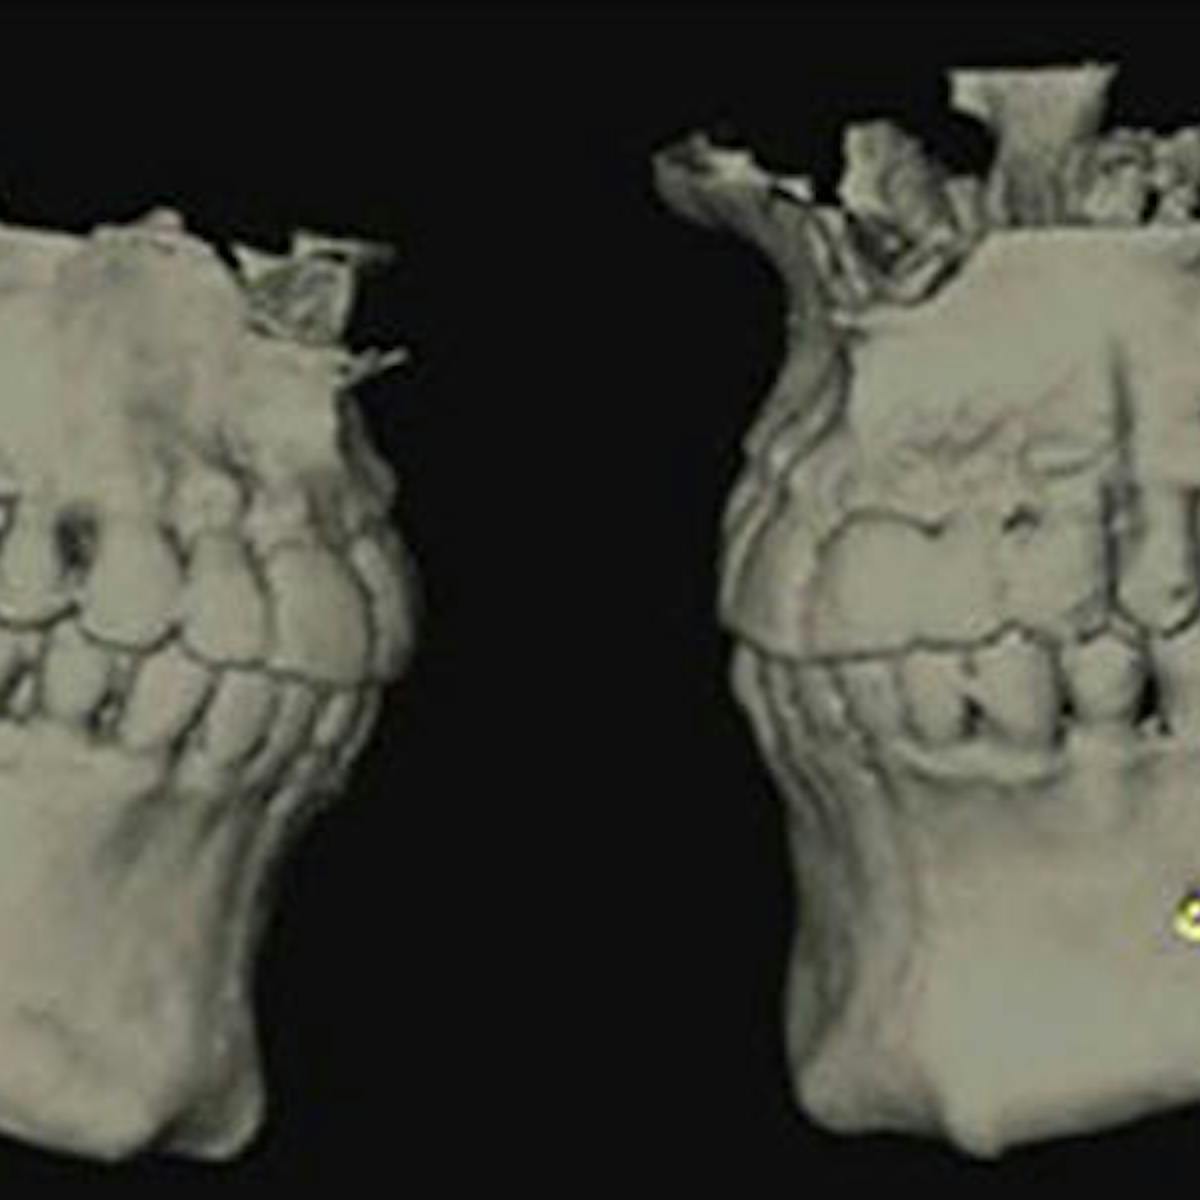

In another example, a young patient had been using e-cigarettes for five years. He started vaping as a method to quit smoking traditional tobacco products thinking vaping was a healthy alternative. Because of its ease of use, he smoked a cartridge of one of the more popular vaping products a day. Admittedly, he also drank energy drinks (high sugar content), stating that his mouth was often dry after vaping. This combination led to rampant decay with smooth-surface lesions and future tooth loss (figure 3).

Figure 3: Effects of e-cigarettes